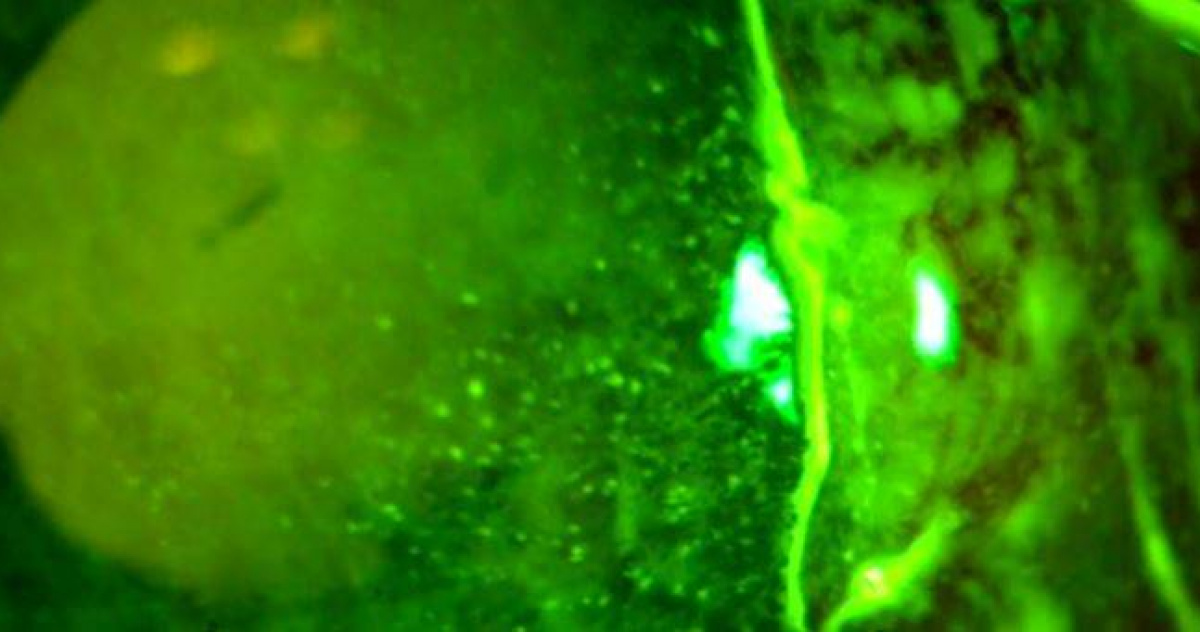

標題: 騎車遭蚊蟲飛入眼!男直覺「1動作」慘了 角膜差點爛穿險失明

角膜